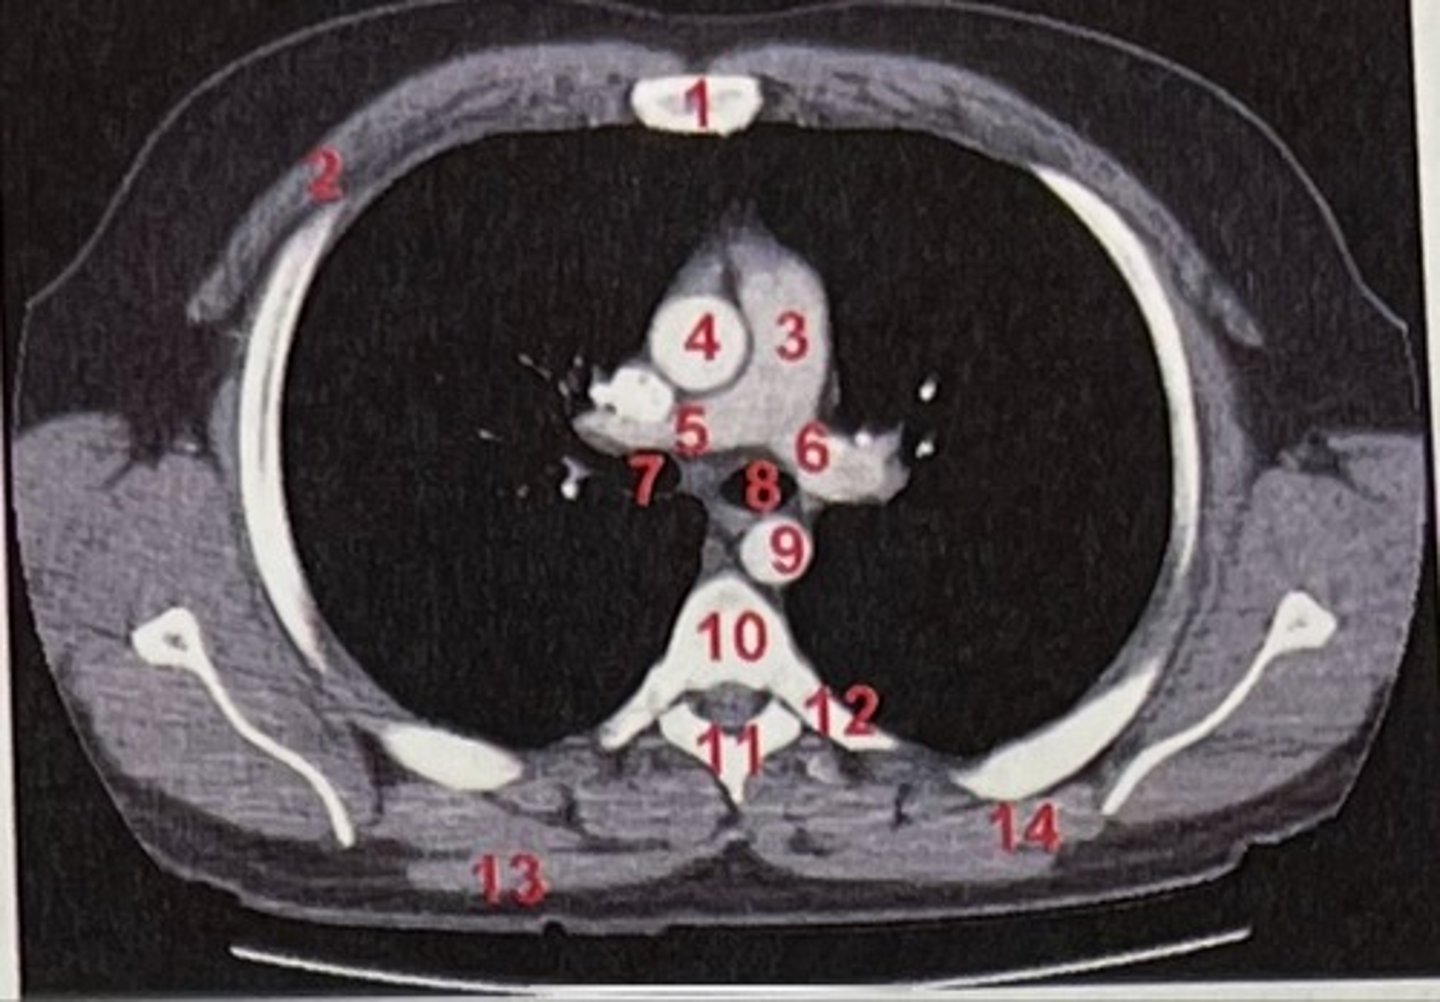

Sternum

What is 1

pectoralis major

What is 2

Pulmonary trunk

What is 3

Right and left pulmonary arteries

What is 5 and 6

Ascending aorta

What is 4

right primary bronchus, left primary bronchus

What is 7 and 8

Descending aorta

What is 9

Rhomboid major

What is 14